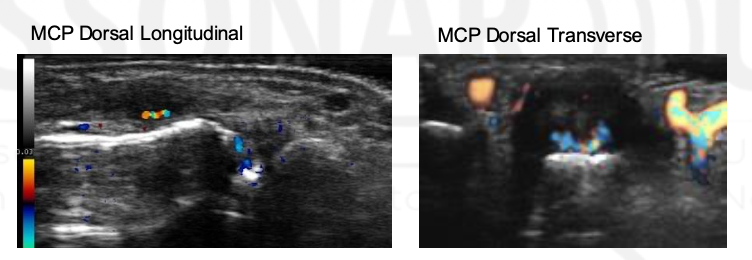

Grade this doppler

Grade 2: Larger than grade 1 + <50% of SH area

Grade 3: >50% of the synovial hypertrophy is covered by signals